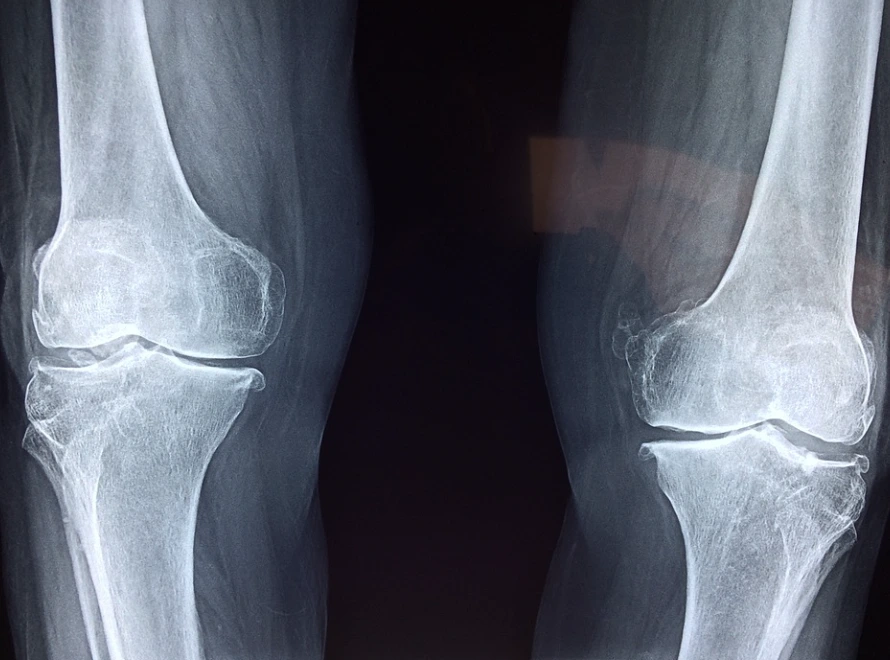

체중이 1kg 오르면 무릎 관절이 받는 부하가 3kg 정도 증가한다고 합니다. 대중교통을 타고 다니는 직장인의 경우에는 어쩔 수 없이 서있는 시간이 많은데, 장기간 지속되면 무릎이나 발목 관절 건강이 더 안 좋아질 수 있습니다. 대중교통을 타지 않아도 되는 직장인은 타는 직장인보다 덜할 뿐이지 관절은 지속적으로 데미지를 받게 됩니다.